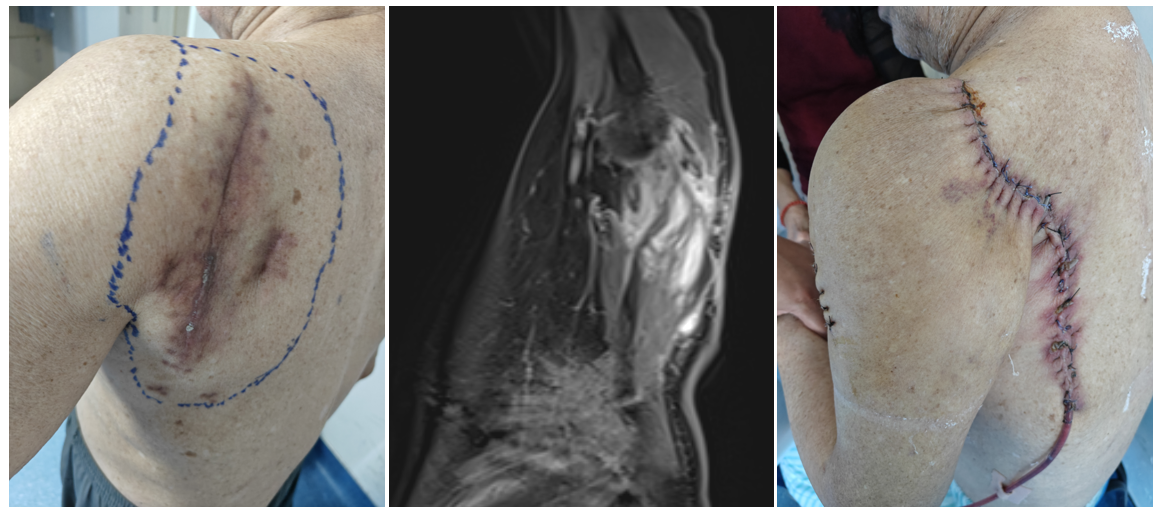

案例一 左上臂粘液纤维肉瘤(术后复发),行肿瘤扩大性切除,使用带血管蒂的背阔肌皮瓣转移作软组织修复。